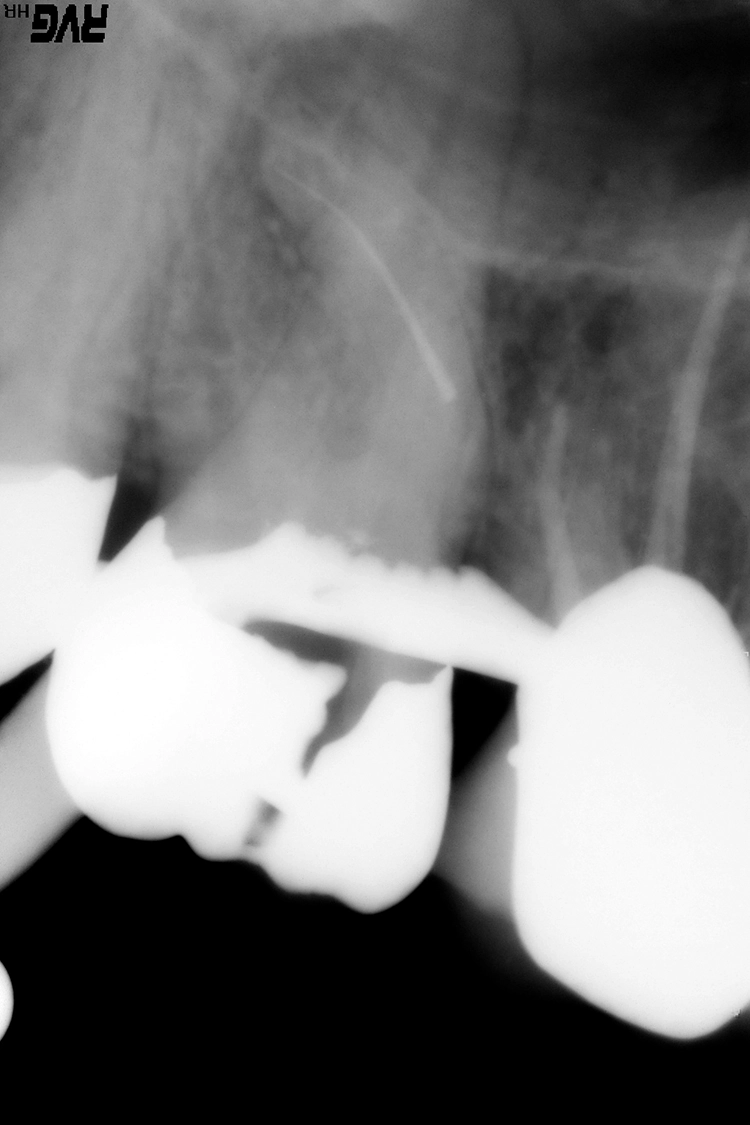

Die Schwierigkeit der mechanischen Ausformung eines Wurzelkanals steigt mit zunehmendem Krümmungswinkel und abnehmendem Krümmungsradius an (Abb. 1). Eine koronale Lokalisierung der Krümmung erhöht die Wahrscheinlichkeit einer Instrumentenfraktur im Vergleich zu einer Krümmung des Wurzelkanals im mittleren oder apikalen Wurzeldrittel [2] (Abb. 2).

Deutlicher zeitlicher Mehraufwand liegt häufig in prozessualen Fehlern, wie bspw. übermäßigem Zahnhartsubstanzabtrag, begründet. Dieser kann zu Kanalverlagerungen und -perforationen führen (Abb. 3a und b), die ein erhöhtes Risiko für anschließende Wurzellängsfrakturen sowie den Verlust des Zahnes darstellen können [12].